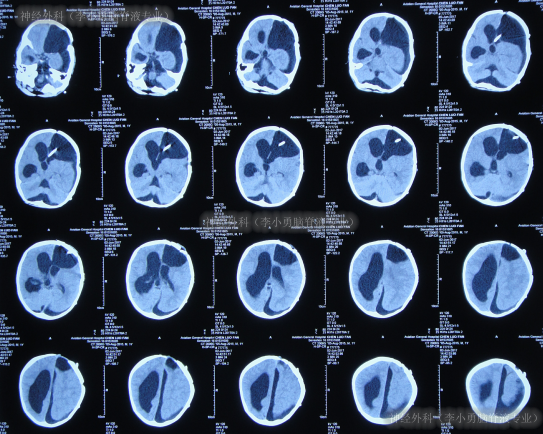

第4次手术脑室腹腔分流术后3天即2017年6月23日,查头颅CT示脑室仍扩张(图-13)。

图-13:2017年6月23日头颅CT

第4次手术脑室腹腔分流术后20天即2017年7月10日,查头颅CT示脑室再次扩张更大(图-14)。

图-14:2017年7月10日头颅CT